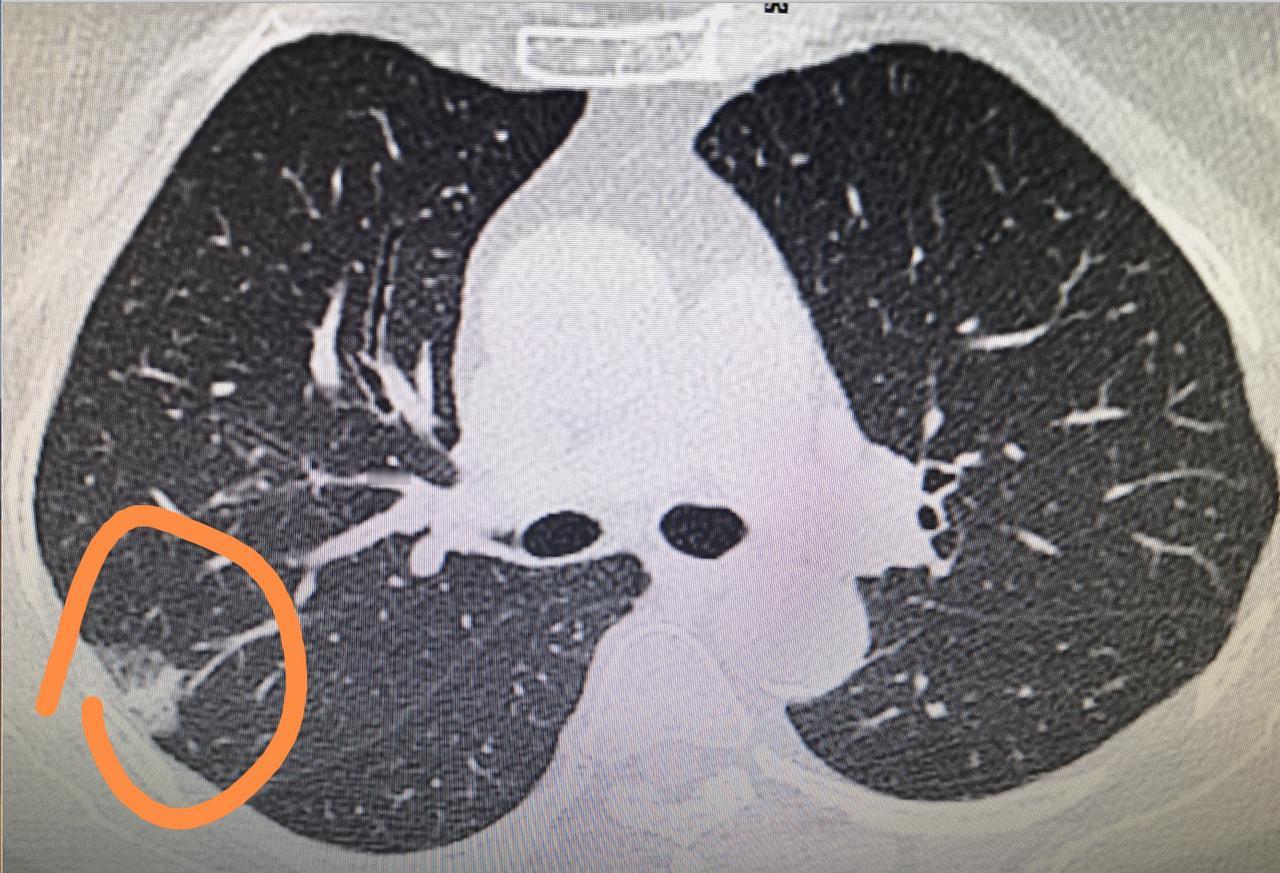

[心]肺结节的6种描述,这次教会你看!会看了不用四处求人! 描述1:边界清 多是

肺部CT出现这5种情况,恭喜你,先不用治!关注肺结节 健康 肺